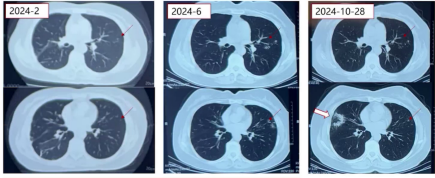

3.胸部CT

3)2024年6月:左肺上叶小结节影、斑片影及左下叶小结节较前加重。

4)2024年10月28日:右肺中叶新发胸膜下实变影,左肺上叶小结节影较前稍减轻。

2024年6月复查CT,右肺实变影进一步吸收,但左肺树芽征、小结节影及斑片影加重,患者口服左氧氟沙星2周,复查CT无明显变化,再次行气管镜检查:BALF抗酸染色、结核分枝杆菌液体培养均阴性,mNGS检出脓肿分枝杆菌(1条序列),同期BALF核酸提取物T-SPOT.TB检出脓肿分枝杆菌(5万余条序列)。

2024年7月,患者减停泼尼松,继续口服异烟肼、利福平;2024年10月28日复查胸部CT,示右肺中叶新发胸膜下实变影,左肺上叶树芽征及斑片影较前稍减少,为进一步明确诊断入院。